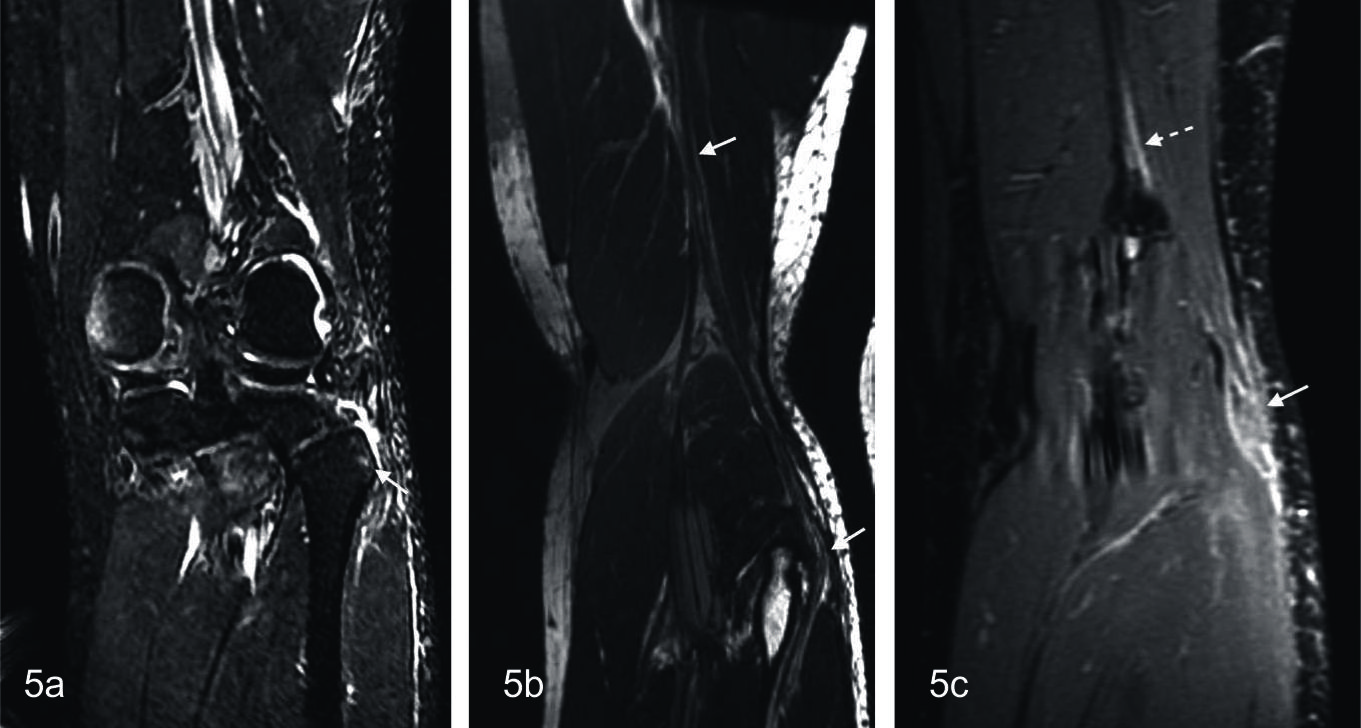

Figura 5

Neuroma por contiguidad:

Paciente masculino de 25 años con antecedente de trauma en rodilla. (A) secuencia IDEAL water ponderada en T2, muestra edema en la cabeza del perone (flecha) y partes blandas adyacentes, (B) secuencia FIESTA 3D con reconstrucción curva, donde se observa al nervio peroneo comun (flechas) que presenta engrosamiento pseudonodular a la altura de la cabeza del perone (neuroma), (C) secuencia IDEAL 3D en ponderación T1 tras la administración de contraste, que muestra realce del nervio peroneo proximal (flecha entrecortada) y leve realce periférico del neuroma (flecha), en relacion a cambios inflamatorios.

En la neurotmesis puede identificarse la falta de continuidad del nervio en estadíos agudos, aunque puede dificultarse debido a la presencia de cambios inflamatorios y hemorragia perilesional. En el estadio crónico puede observarse el neuroma en continuidad, que se describe como una lesión redondeada de baja señal en ponderaci ón T2 en el trayecto del nervio. Puede ser confundido con un tumor de la vaina nerviosa, aunque el neuroma no refuerza tras la administración de contraste (28). Los pacientes con neurotmesis no se recuperan y su pronóstico depende de la pronta y apropiada conducta quirúrgica. En este caso la NRM es útil para la adecuada caracterización del trayecto anatómico comprometido y la clasificación de la lesión, lo que contribuye al resultado clinico (Fig. 5).